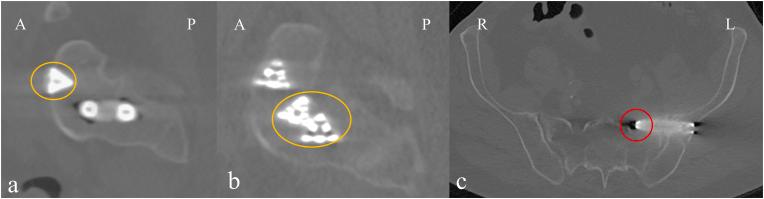

Sacroiliac (SI) dysfunction causes of up to 30 % of lower back pain. When conservative treatment is insufficient, SI joint fusion (SIJF) can be indicated to reduce pain. Due to high anatomical variability, poor visibility during intraoperative 2D fluoroscopic imaging, and the absence of 3D spatial information, placing the implant in a stable configuration without damaging critical structures is challenging. To improve patient outcomes, a virtual surgical planning (VSP) method using simulated fluoroscopic images has been developed.

This retrospective case-control study compared procedures performed with VSP to those conducted prior to its implementation. Data were collected from the medical records, Numeric Rating Scale (NRS) questions, and patient reported outcome measures (PROMs). All postoperative CT scans were assessed on implant placement (mal)positioning and fractures. Malposition complications were categorized as severe malposition and suboptimal implant placement.

RESULTS

骶髂关节功能障碍导致高达30%的下背部疼痛。当保守治疗无效时,可考虑进行骶髂关节融合术(SIJF)以减轻疼痛。由于解剖变异大、术中二维透视成像时视野不佳以及缺乏三维空间信息,在不损伤关键结构的情况下将植入物放置在稳定的位置具有挑战性。为改善患者预后,已开发出一种使用模拟透视图像的虚拟手术规划(VSP)方法。

方法

这项回顾性病例对照研究将采用VSP进行的手术与实施VSP之前进行的手术进行了比较。数据从医疗记录、数字评分量表(NRS)问题以及患者报告的结局指标(PROMs)中收集。所有术后CT扫描均评估植入物的放置(错)位置和骨折情况。位置不当并发症分为严重位置不当和植入物放置欠佳。

结果